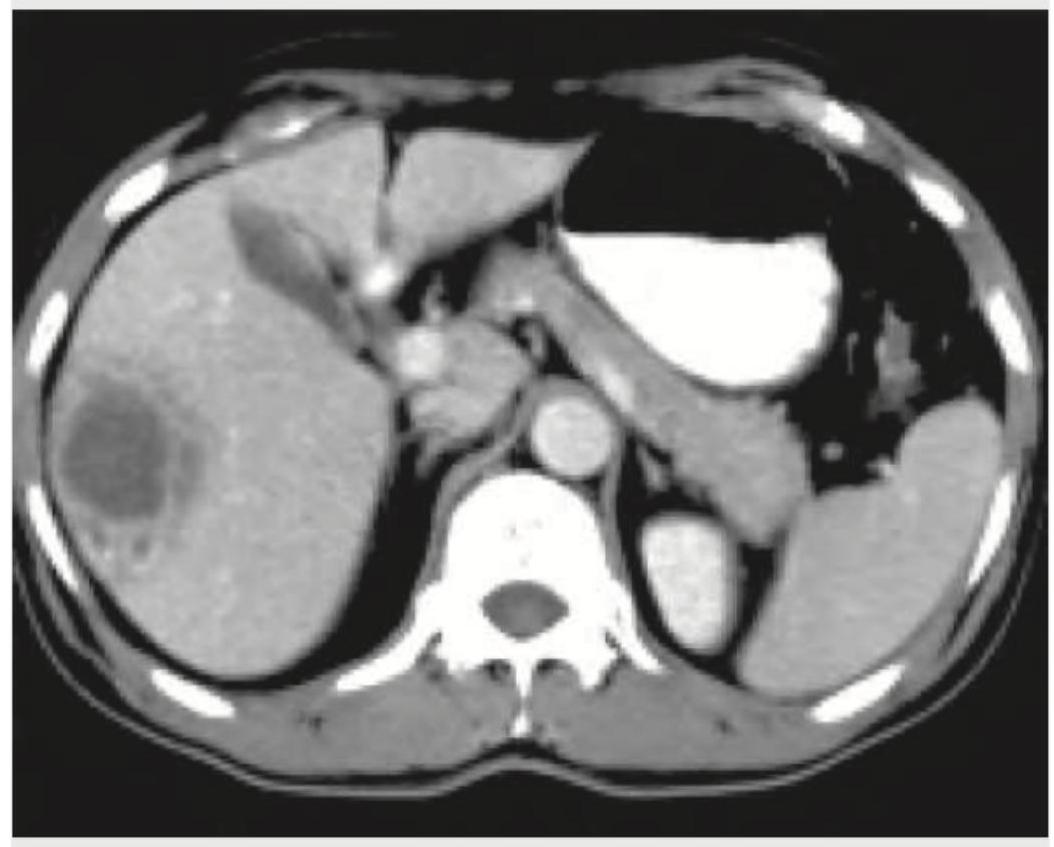

The CT abdomen of a 10-year-old child with high grade fever for last 5 days shows:

Explanation: ***Liver abscess*** - The CT image shows a well-defined, **hypodense lesion** within the right lobe of the liver, consistent with the characteristic appearance of a **liver abscess**, especially in a child presenting with **high-grade fever**. - Liver abscesses are collections of pus that can form in the liver, often presenting with fever, abdominal pain, and leukocytosis. *Typhlitis* - This condition involves inflammation of the **cecum** and ascending colon, often seen in **immunocompromised patients** (neutropenic enterocolitis). - CT findings would typically show **cecal wall thickening** and surrounding inflammation, which is not depicted in the image. *Acute pancreatitis* - This is an inflammation of the pancreas, usually presenting with severe **epigastric pain** radiating to the back. - CT findings would include **pancreatic edema**, fat stranding, and potentially fluid collections around the pancreas, none of which are evident in the provided image. *Biloma* - A biloma is a collection of **bile** that occurs due to leakage from the biliary tree, usually after trauma or surgery. - While it appears as a fluid collection, it typically lacks the often **irregular enhancing rim** or internal septations sometimes seen in abscesses, and the clinical context of high fever points more towards an infectious process.